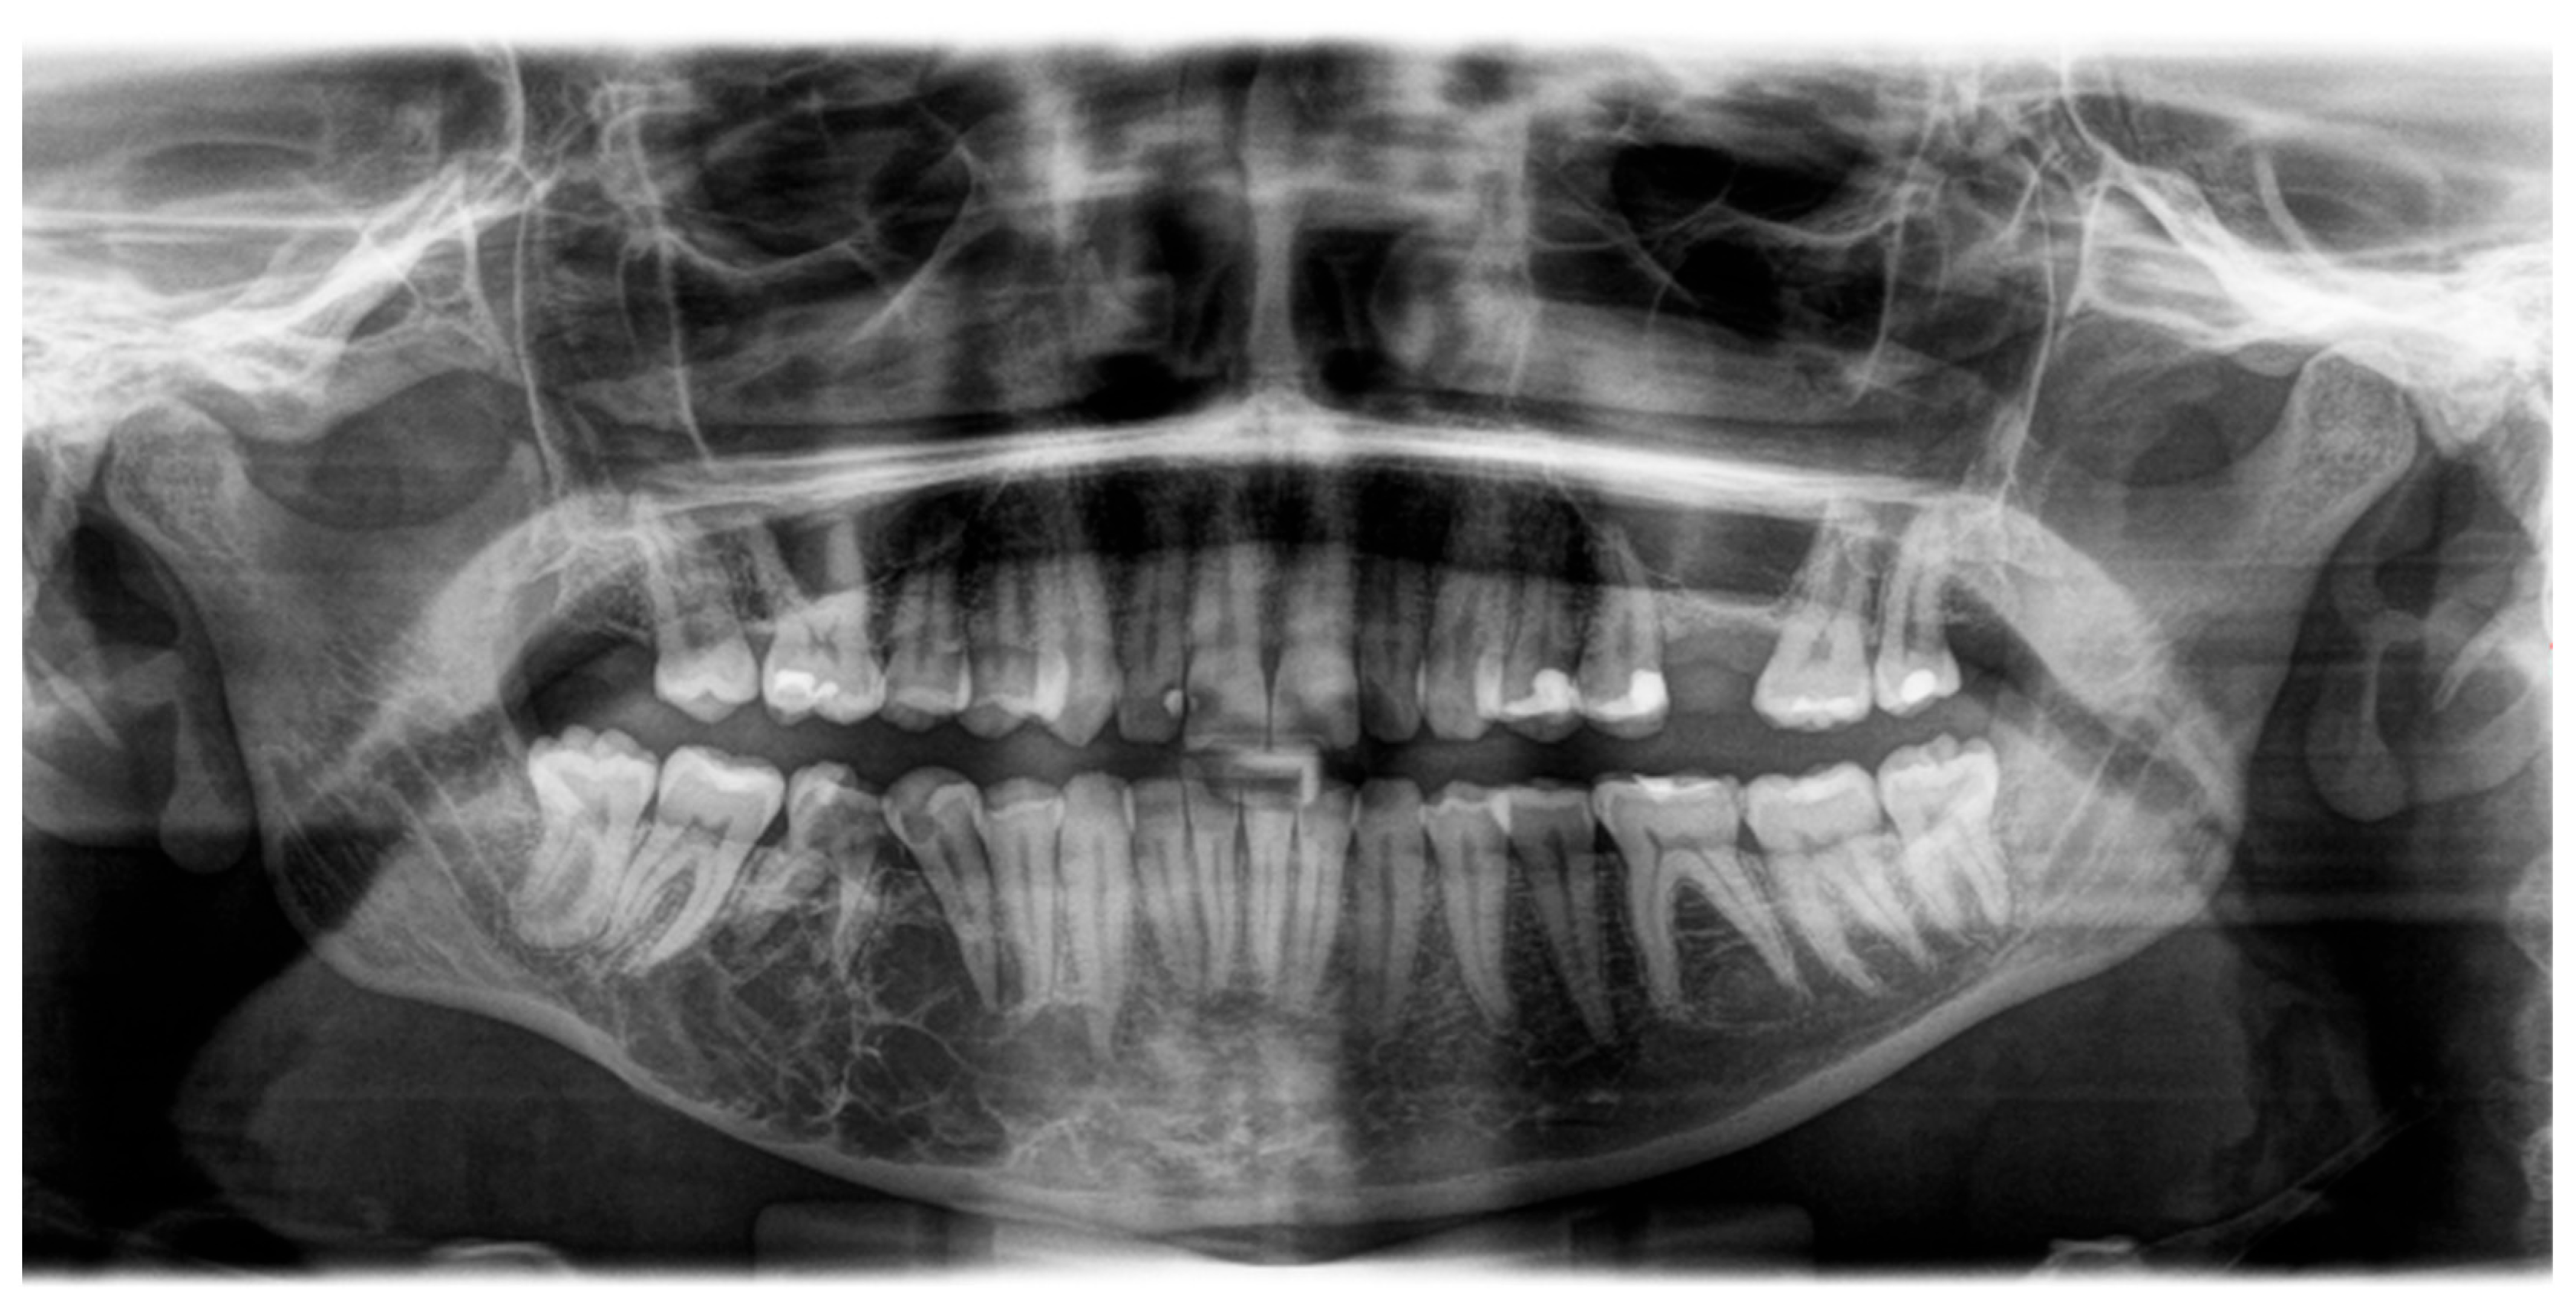

2. Case Report

2.1. Examination

2.2. Treatment Procedures and Histopathological Results